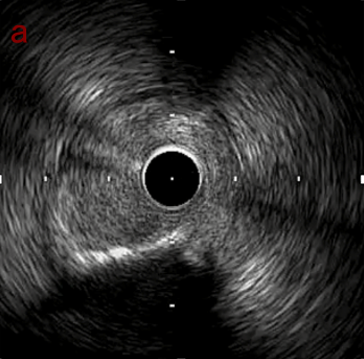

IVUS imaging

IVUSでは8時方向からPD枝がはいいてくる。

PreのIVUSではaの部位のみlipid plaqueを認め削ることでdistal embolismのリスクがあり、そのほかは270度の偏心性石灰化であるがwire biasは良好。